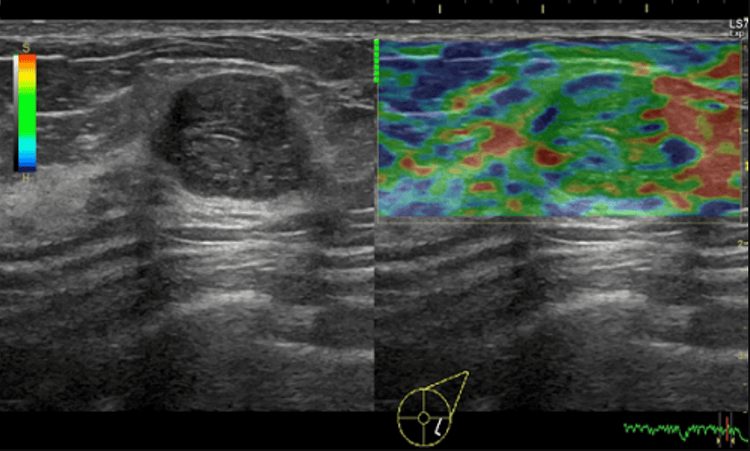

Siêu âm đàn hồi mô là kỹ thuật siêu âm giúp cho bác sĩ đánh giá được độ cứng của mô thông qua mức độ đàn hồi của mô khi chịu một tác động của lực cơ học. Các mô bệnh lý có thể cùng độ hồi âm, nhưng sẽ có độ cứng khác nhau, các mô càng ác tính thì độ cứng sẽ càng tăng lên. Chính vì thế, khi đánh giá được độ cứng của mô tổn thương sẽ cung cấp thêm thông tin về bản chất của mô đó.

Phương pháp siêu âm đàn hồi mô bằng cách tác động một lực từ bên ngoài lên tổn thương để gây ra biến dạng tổn thương như trên được gọi là tạo hình đàn hồi bán tĩnh hay còn gọi là đàn hồi gây biến hình. Khi thực hiện kỹ thuật, người làm siêu âm ấn đầu dò bằng một lực nhất định để tác động lên mô tổn thương.

● Bước 3: Khi thực hiện siêu âm tuyến vú, người thực hiện siêu âm ấn đầu dò bằng một lực nhất định để tác động lên mô tổn thương. Sau đó sử dụng chùm sóng siêu âm tần số 50Hz vào mô tổn thương để xác định mô tổn thương.

● Bước 4: Kỹ thuật thực hiện trong khoảng 5 đến 10 phút. Đầu dò siêu âm sẽ thu nhận và mã hóa ra sóng bằng màu sắc giúp bác sĩ lượng hóa được độ cứng của mô.